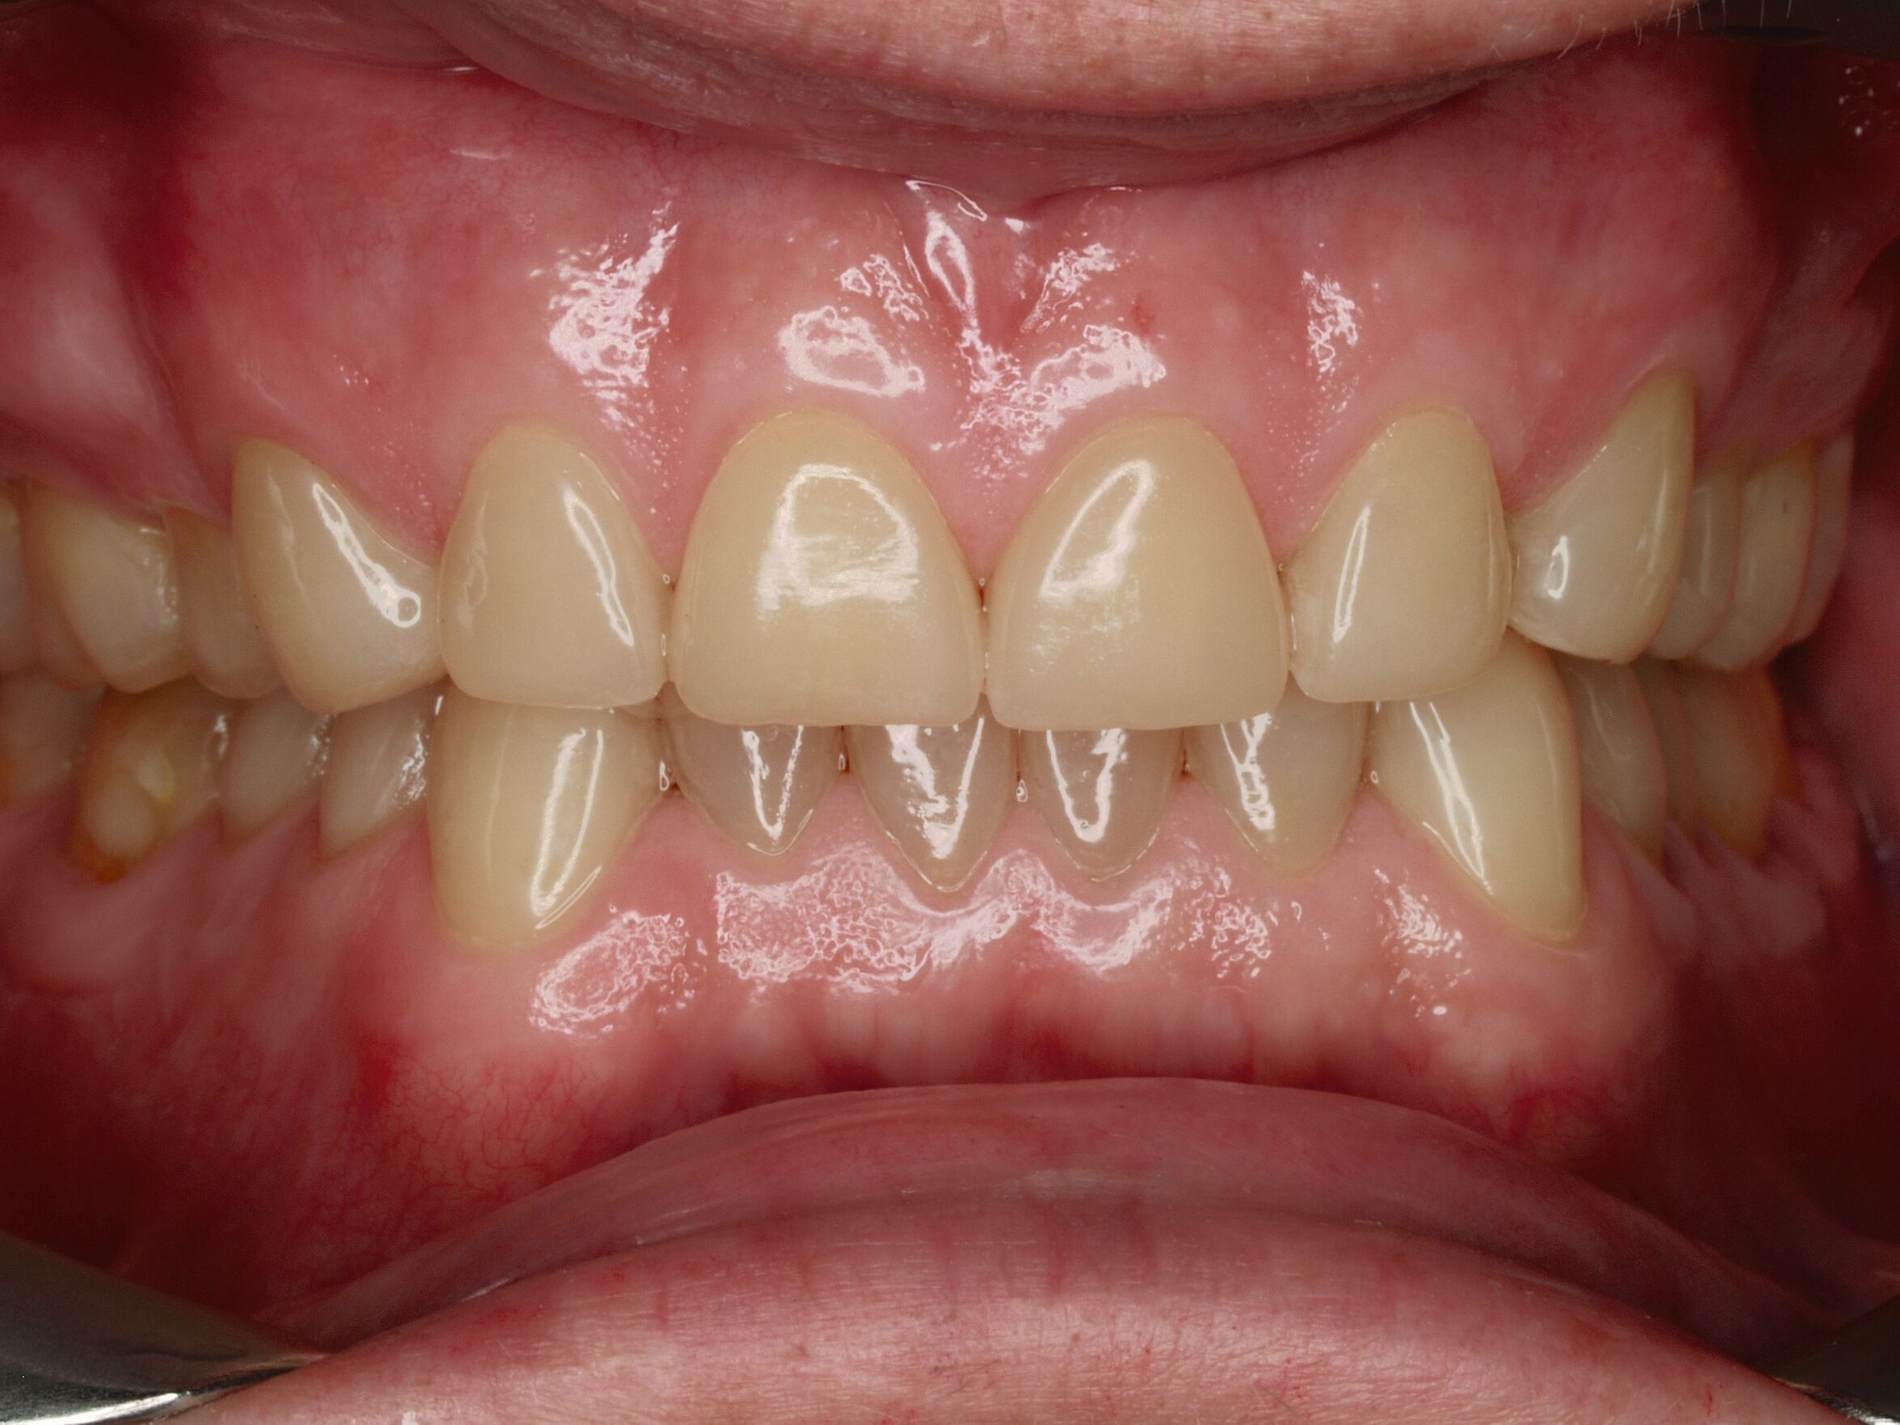

Auch wenn Restaurationen nach Möglichkeit vermieden werden sollten, ist deren Verfügbarkeit für die Betroffenen individuell höchst wichtig, weil sie bestehende Schmerzen beseitigt, die verlorengegangene Kauleistung wiederherstellt und ästhetische und nicht zuletzt auch phonetische Einschränkungen aufhebt. Bei dem in den Abbildungen beschriebenen Fall korrelierte der erhebliche Zahnverschleiß mit der Lokalisation der Zahnschmerzen des Patienten. Direkte Restaurationen mit Kompositen hatten keinen Bestand. Die durchgeführte restaurative Behandlung hingegen hat Bestand, die Schmerzen waren danach umgehend verschwunden und sind seit zehn Jahren nicht wiedergekehrt.

Dabei führt die Verfügbarkeit hochfester Dentalkeramiken heute zu viel weniger invasiven Restaurationen als früher durchgängig übliche metallkeramische Kronen, und die Transluzenz der keramischen Werkstoffe ermöglicht zudem natürlichere Restaurationen. Der beschriebene Behandlungsfall zeigt, wie eine mehrstufige Zahnverschleiß-Diagnostik im Praxisalltag umgesetzt wird, mit initialem Zahnverschleiß-Screening und einer im Bedarfsfall erfolgenden erweiterten Diagnostik per Zahnverschleiß-Status.

Nach der Eingliederung der Restaurationen hat sich eine umgehende Abformung bewährt, die ebenso umgehend in Modelle überführt wird, um zu prüfen, ob die Restaurationen gleichmäßig aufeinandertreffen. Beim Folgetermin zum Finetuning liegen diese dann vor und erlauben im Zweifelsfall eine umgehende okklusale Korrektur. Wichtig ist, den sensorischen Eingewöhnungsstress der Patienten abzufangen. Das gelingt am Tag der Eingliederung durch eine hydrostatische Sofortschiene (The Aqualizer, Bausch Dental, Köln; AquaSplint mini, TeleDenta, Chemnitz; FreeBite Gel, MediPlus, Unterleinleiter). Spätestens nach dem Finetuning erfolgt eine neue Abformung als Grundlage für die Herstellung einer neuen Okklusionsschiene. Die AWMF-Leitlinie zu vollkeramischen Kronen und Brücken verlangt, dass diese bei Bruxismus zum Schutz der Restaurationen dauerhaft getragen wird. Diese Okklusionsschiene kann im Ober- oder Unterkiefer getragen werden, die eingestellte Kieferposition entspricht der durch die Restauration eingestellten Position.